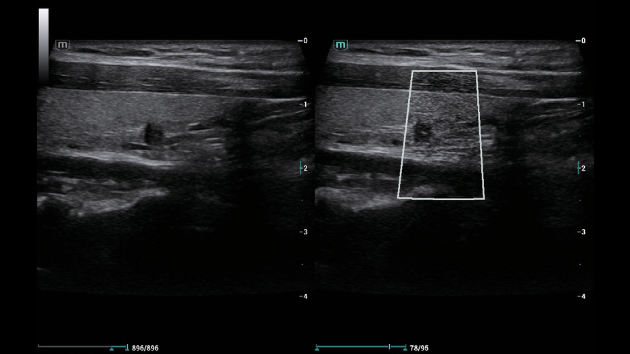

HD Scope: передовая технология повышения разрешения для точной диагностики

HD Scope — это инновационная функция, повышающая пространственное разрешение в выбранной области интереса (ROI) за счет улучшения четкости и детализации изображения. Она позволяет врачам сосредоточиться на конкретных структурах, таких как мелкие сосуды или патологические образования, без потери общего контекста снимка. Технология сокращает время диагностики, так как исключает необходимость повторного сканирования для уточнения деталей. Например, при исследовании печени HD Scope помогает дифференцировать гиперэхогенные очаги, улучшая точность оценки стеатоза. Встроенная в систему ZST+, HD Scope в Consona N6 поддерживает многопрофильные исследования — от кардиологии до онкологии, обеспечивая высокую диагностическую ценность для клиник.

HD Scope: передовая технология повышения разрешения для точной диагностики

HD Scope — это инновационная функция, повышающая пространственное разрешение в выбранной области интереса (ROI) за счет улучшения четкости и детализации изображения. Она позволяет врачам сосредоточиться на конкретных структурах, таких как мелкие сосуды или патологические образования, без потери общего контекста снимка. Технология сокращает время диагностики, так как исключает необходимость повторного сканирования для уточнения деталей. Например, при исследовании печени HD Scope помогает дифференцировать гиперэхогенные очаги, улучшая точность оценки стеатоза. Встроенная в систему ZST+, HD Scope в Consona N6 поддерживает многопрофильные исследования — от кардиологии до онкологии, обеспечивая высокую диагностическую ценность для клиник.